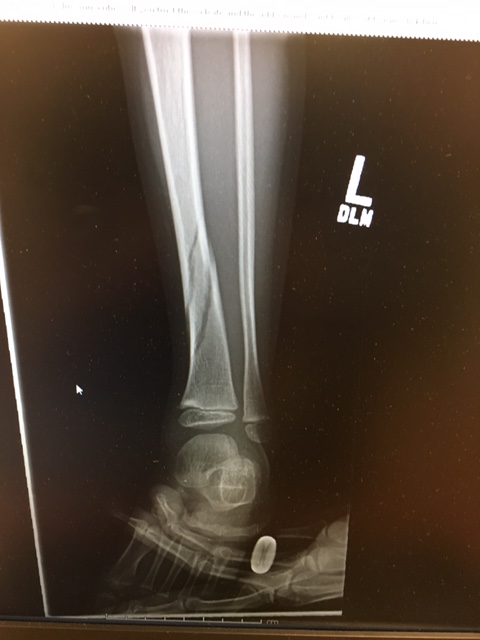

The xray came back and showed a spiral fracture of his tibia. In between seeing and caring for my other patients I grabbed a couple of our ED techs and asked them to put his splint on. I held him and talked him through the splint which he was not happy about and everything hurt. Added to being very very tired I’m pretty sure most of the town could hear him crying and screaming. At one point he looked up and just cried out “I’m just so very very angry”. It broke my heart.